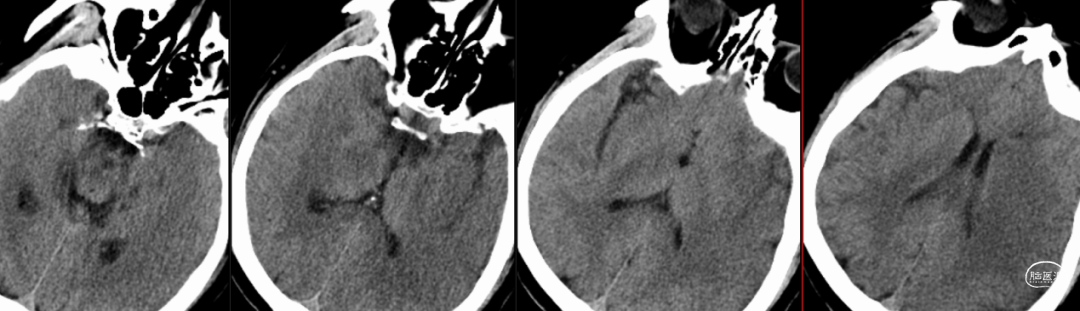

头颅CT(12/3):左侧颞叶可以低密度影,左侧大脑中动脉可疑高致密征。

头颅CTA(12/3):左侧大脑中动脉闭塞。

术前造影提示:左侧大脑中动脉闭塞,可见部分豆纹动脉显影,左侧大脑前动脉通过脑膜支代偿左侧大脑中上干。